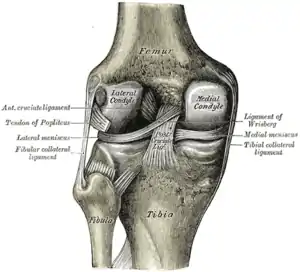

Diagram of the right knee

Pathophysiology

The knee joint is formed by three bones: the femur (thighbone), the tibia (shinbone), and the patella (kneecap). These bones are held together by ligaments, which are strong bands of tissue that keep the joint stable while an individual is walking, running, jumping, etc. There are two types of ligaments in the knee: the collateral ligaments and the cruciate ligaments.

The collateral ligaments include the medial collateral ligament (along the inside of the knee) and the lateral or fibular collateral ligament (along the outside of the knee). These two ligaments function to limit sideways movement of the knee.[6]

The cruciate ligaments form an “X” inside the knee joint with the anterior cruciate ligament running from the front of the tibia to the back of the femur, and the posterior cruciate ligament running from the back of the tibia to the front of the femur. The anterior cruciate ligament prevents the tibia from sliding out in front of the femur and provides rotational stability.[6]

There are also two C-shaped structures made of cartilage called the medial meniscus and lateral meniscus that sit on top of the tibia in the knee joint and serve as cushion for the bones.[1]

Right knee, front, showing interior ligaments Left knee, behind, showing interior ligaments